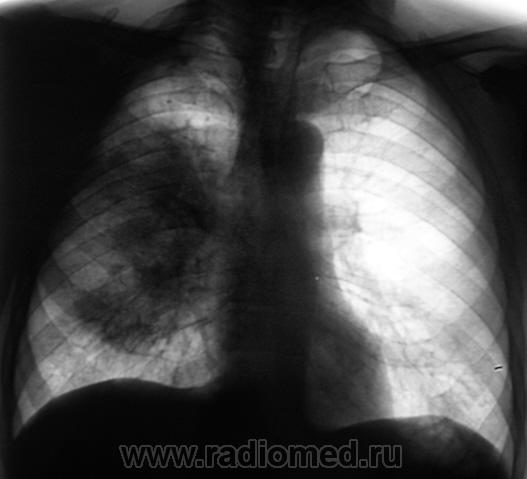

При расшифровки цифровых флюорограмм пациент "взят на контроль". Смутила правая верхушка и верхняя доля правого лёгкого.

Произведено дообследование.